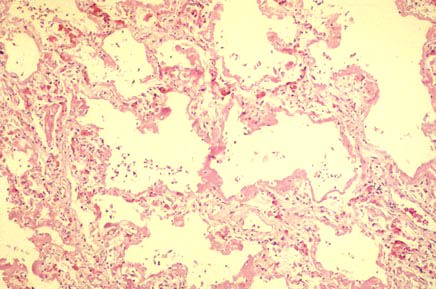

Low power photomicrograph of adult respiratory distress syndrome (ARDS) showing hyaline membranes and interstitial edema.